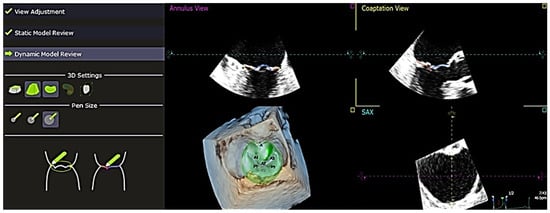

The software used to analyze the 4D echocardiography data was QLAB 13, an experimental, unreleased software developed by PHILIPS and TomTec, which was approved by the FDA on 18 June 2019. A set of Q-apps analysis tools equipped in the software could be selected for the quantitative analysis of echocardiographic data. These tools included 4D Mitral Valve Assessment (MVA), Mitral Valve Navigation (MVN), General Imaging 3DQ (GI3DQ), etc. The MVA feature was used to perform echo analysis, allowing the extraction of essential variables for the study. The positions of the mitral valve annulus and leaflets were automatically generated by the software, outlined using “points” and “lines” superimposed on the approximated margins of the mitral valve, as shown in Figure 1. These “points” and “lines” could be adjusted manually to gain a more accurate approximation of the actual position of the mitral valve using the next three stages of review, namely, view adjustment, static model (Figure 2), and dynamic model (Figure 3) reviews.

In addition to this, QLAB 13 also had the ability to perform quantitative analysis on a single frame throughout the cardiac cycle to obtain other parameters such as Ch-A, Ch-P, and inter-papillary distance. Mitral valve measurements were obtained after completing these stages (Figure 4). The results were exported in .txt format and arranged into measurement groups: “Annulus”, “Leaflets”, “Coaptation”, “Miscellaneous”, “Manual Measurements”, and “Dynamic Measurements”. These measurements were then extracted and compiled into an Excel sheet, summarizing the data for all 34 patients involved in the study. After collecting the 4D echocardiographic variables of all the patients, the data were compiled and edited meticulously and anonymously. The data were also checked again for any missing values or discrepancies. All omissions and inconsistencies were corrected and removed methodically. Additionally, other variables not derived directly from the software, such as indexed papillary muscle displacement, were manually calculated using the following formula: Indexed papillary muscle displacement = Inter-papillary distance/Body surface area. These values were then included in the data collection form.

Figure 3. “Dynamic Model Review” shows alignment in the generated dynamic model review—this provides the visualization of both annulus and coaptation once the “Static Model Review” is completed. Both the “Static Model Review” and “Dynamic Model Review” play an important role in the visualization of the valvular complex and its geometric properties. A1, A2, A3 = anterior leaflet, P1, P2, P3 = posterior leaflet, SAX = short axis.